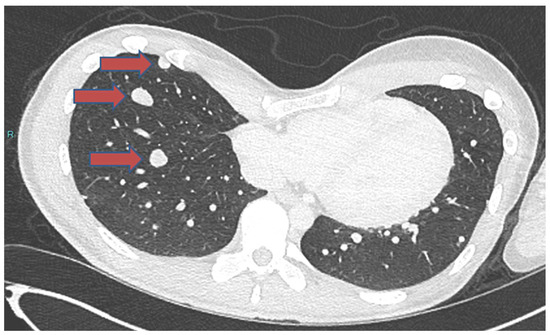

- Focaccia, M.; Gambarotti, M.; Hakim, R.; Paioli, A.; Cesari, M.; Spazzoli, B.; Spinnato, P.; Donati, D.; Rocca, M.; Longhi, A. Chondroblastoma’s Lung Metastases Treated with Denosumab in Pediatric Patient. Cancer Res. Treat. 2021, 53, 279–282. [Google Scholar] [CrossRef] [PubMed]

| Focaccia. M. [37] | 16/M | Proximal humerus | Lung | Occurred at initial diagnosis | Benign | 2 years | Alive at final follow-up | Denosumab treatment | |